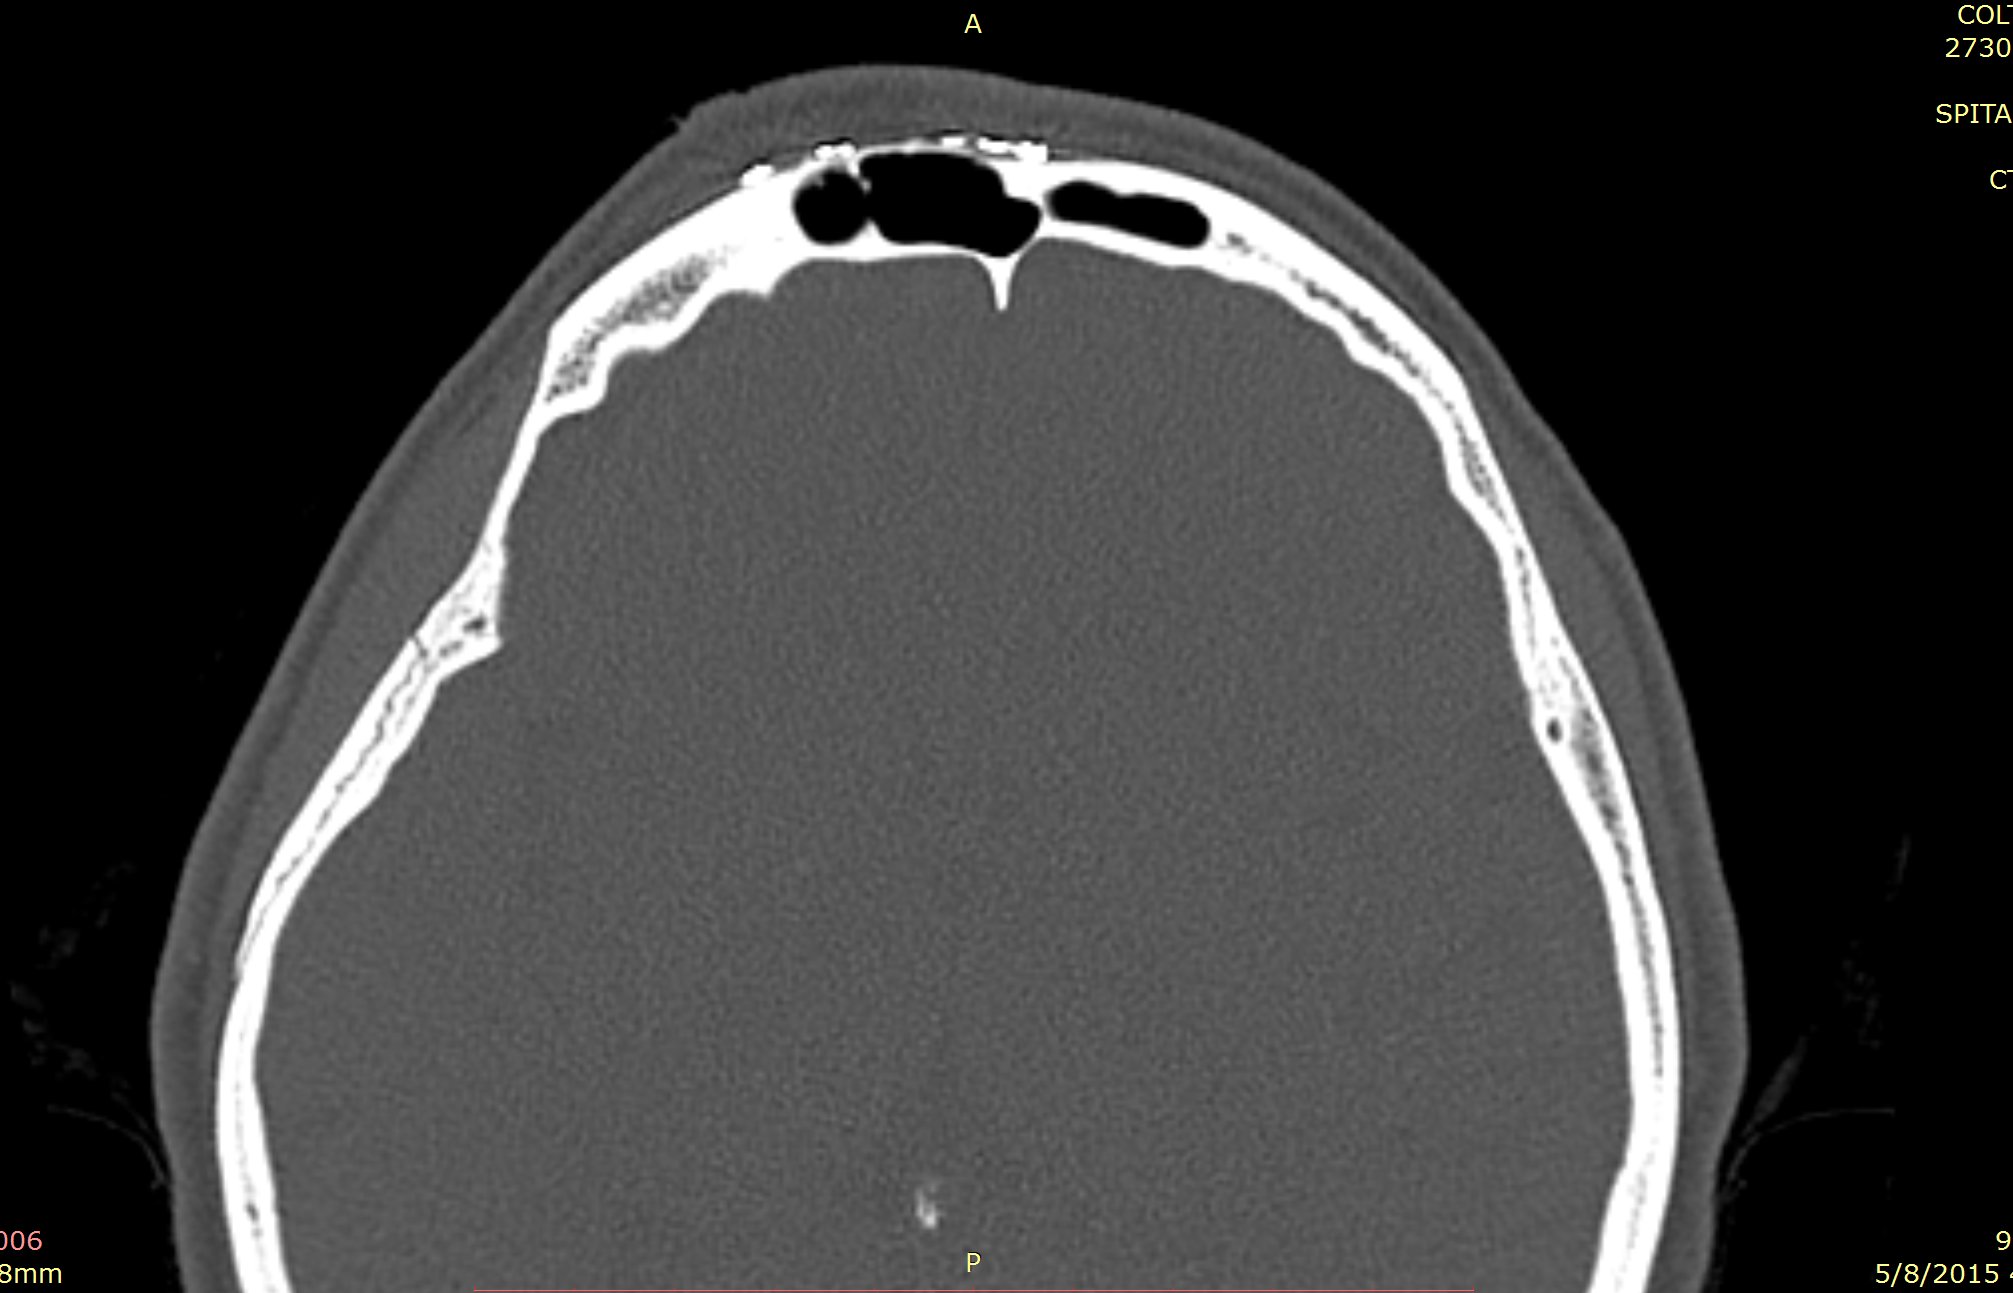

Examenul clinic ORL și examenele imagistice complementare (CT, RMN sinusuri paranazale) pun în evidență o formațiune tumorală osteogenică a sinusului frontal drept, protruzivă în unghiul supero-intern al orbitei, extinsă medial către sinusul frontal stâng.